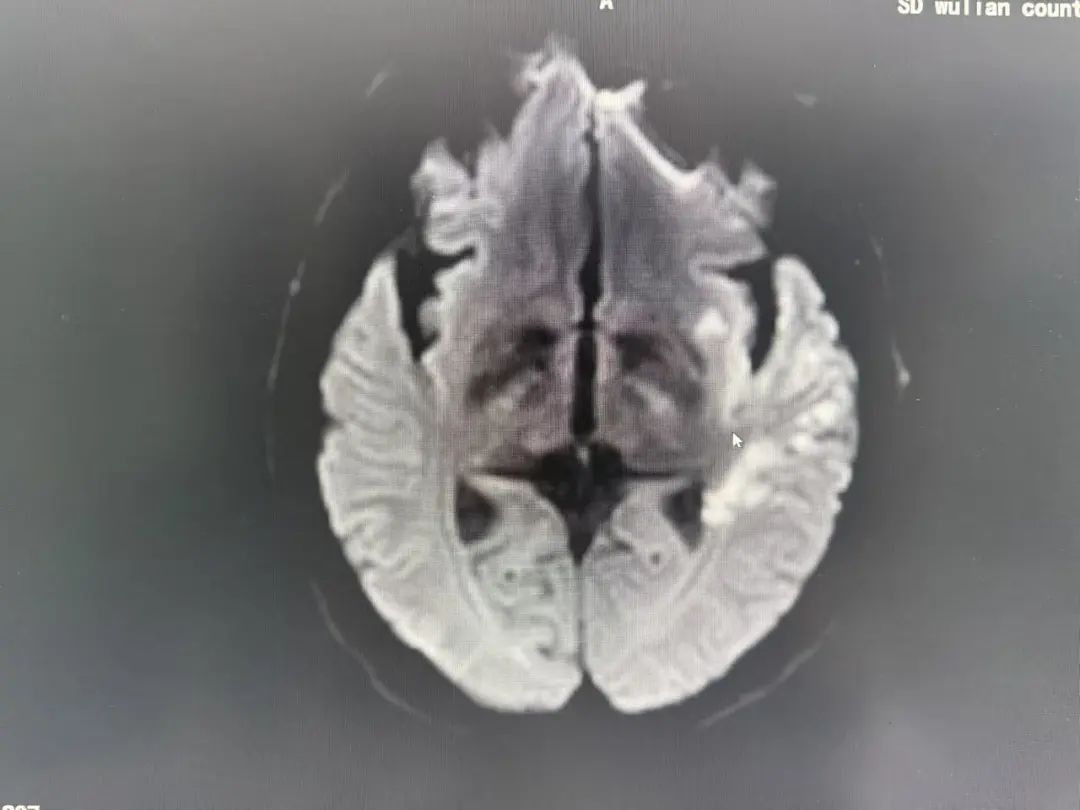

"左侧大脑中动脉闭塞!"

头颈部CTA检查揭开了更凶险的真相:

多发性脑梗死:左侧大脑关键区域受损

血管危机:左侧大脑中动脉闭塞,血流几乎中断

罕见盗血现象:锁骨下动脉重度狭窄,导致血流“偷走”了脑部的供血